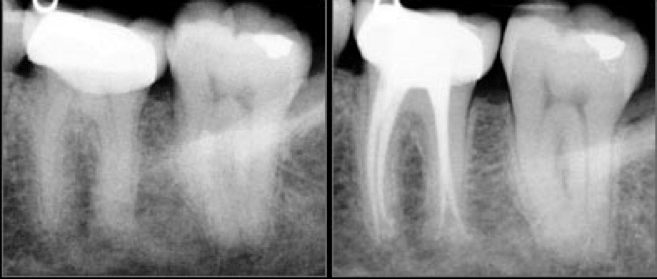

Lorsque la dent est délabrée par la carie de façon très importante et qu'elle est douloureuse de façon irréversible, il faut dévitaliser la dent. C’est à dire qu'il faut enlever la partie du nerf qui est à l’origine de la douleur, on parle alors de « dévitalisation, de traitement de racine ou de traitement endodontique. »

Cette dévitalisation comprend plusieurs étapes :

• enlever le nerf dans toutes les racines

• désinfecter

• reboucher la dent avec un matériau biocompatible

Ce soin est long et complexe. Il nécessite la mise en place d’un champ opératoire (appelé digue) pour isoler la dent des contaminations salivaire, sanguine et bactérienne. La digue permet un certain confort pour le patient et le praticien. Le patient peut déglutir normalement et bien respirer par le nez.